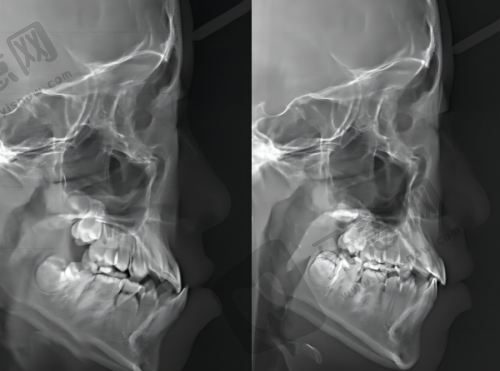

先進正畸技術:採用隱形正畸技術和美觀、舒適、可摘戴;自鎖託槽技術可減少摩擦力,加快牙齒移動速度,縮短治療時間。

全過程管理:治療前全方面檢查評估,制定詳細方案並與患者充分溝通;治療中定期復診,調整矯治器;治療後提供保持器,指導患者佩戴防止牙齒反彈。正畸服務價格從幾千元起到上萬元不等,患者可按需選擇。